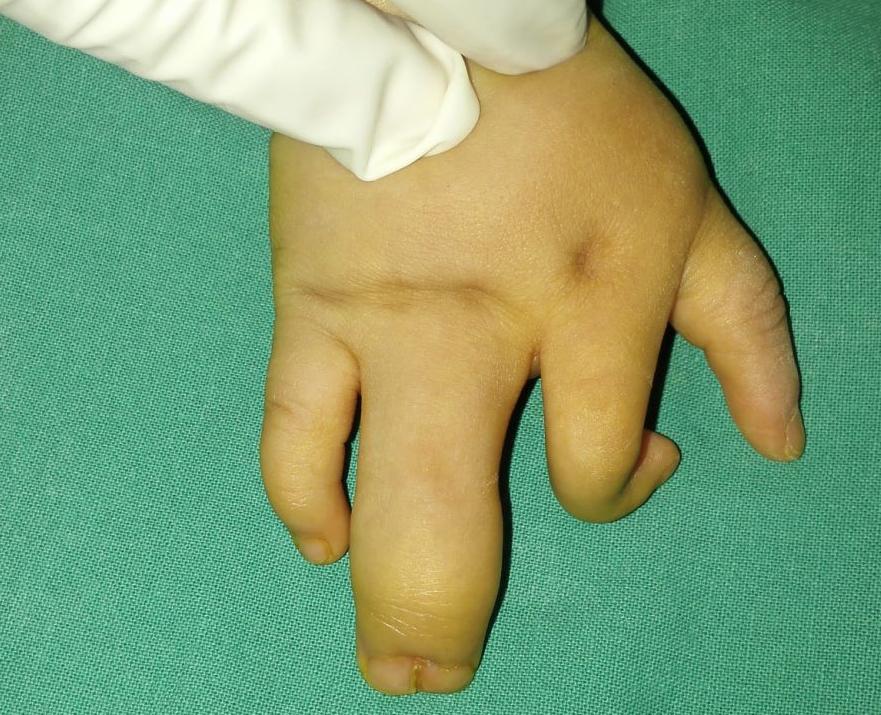

病例3也是一个复杂并指,孩子的手比较小,手指界线不清,远端指骨交叠,拇指往背侧偏移,这样的孩子要尽早手术,因为小手团在一起的时候,孩子的手指关系是异常的,对手指的发育和后期功能建立都有很大的影响。

手术后整体效果不错,我们可以看到孩子整个手指的关系非常清晰,尽管和正常的手还是有差距,拇指比较短,但看起来比较接近正常,拇指的力量、大小、灵活度都不错,复查的时候可以自己拿着水杯喝水了。